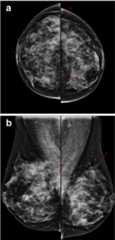

Mammography showing fibrocystic changes: densities typical of fibrocystic disease

Image: “Mammogram Showing Fibrocystic Disease” by National Cancer Institute. License:Public Domain

Mammography showing fibrocystic changes in the left breast of a 50-year-old woman:

Mammography craniocaudal (a) and mediolateral oblique (b) views show regional punctate or microcalcifications (arrows) in the left upper outer and inner quadrant.